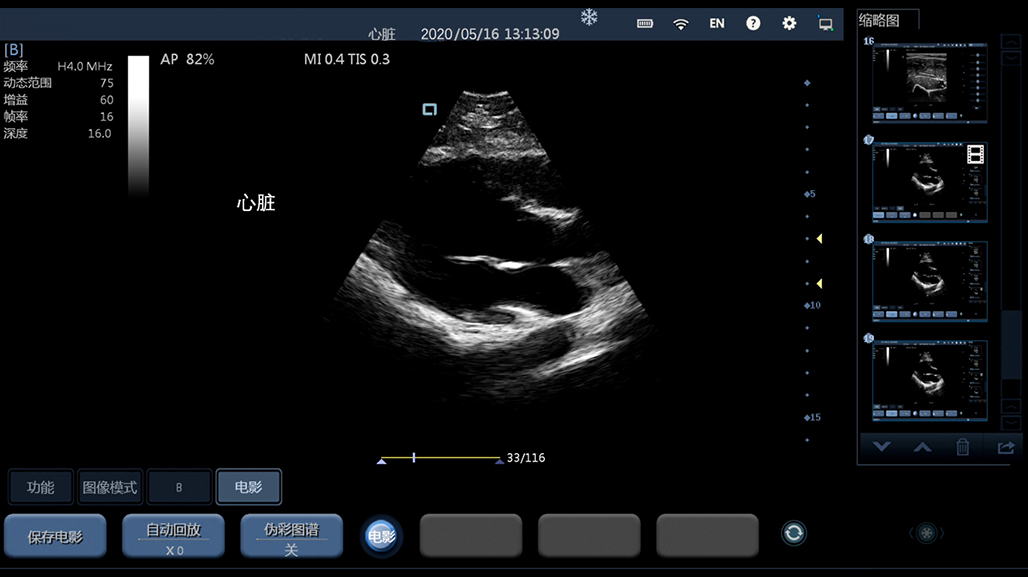

心脏